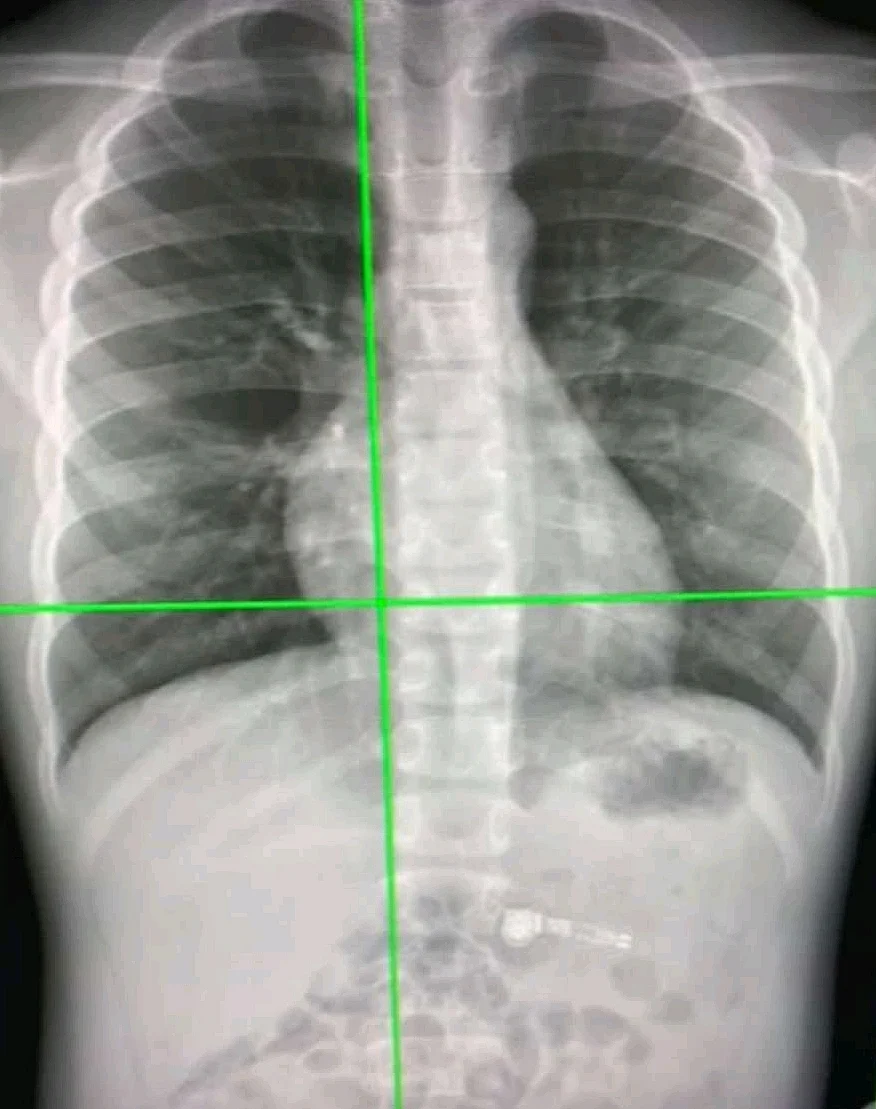

ऑस्ट्रेलियाई शोधकर्ताओं ने एक आर्टिफिशियल इंटेलिजेंस सिस्टम विकसित किया है जो छाती के एक्स-रे से कोविड-19 के संक्रमण को 98 प्रतिशत से अधिक की सटीकता से पता लगा सकता है। यह वर्तमान में उपयोग किए जाने वाले आरटी-पीसीआर परीक्षण की तुलना में अधिक फायदेमंद हो सकता है।

उन्होंने कहा, "नया एआई सिस्टम उन देशों में विशेष रूप से फायदेमंद हो सकता है जहां उच्च स्तर पर कोविड-19 अनुभव हो रहा है, जहां रेडियोलॉजिस्ट की कमी है। चेस्ट एक्स-रे पोर्टेबल हैं, व्यापक रूप से उपलब्ध हैं और सीटी स्कैन की तुलना में कम जोखिम प्रदान करते हैं।"

साइंटिफिक रिपोर्ट्स जर्नल में प्रकाशित एक पेपर में विस्तार से बताया गया है कि नया एआई सिस्टम कस्टम कन्वोल्यूशनल न्यूरल नेटवर्क नामक एक गहन शिक्षण आधारित एल्गोरिदम का उपयोग करता है जो एक्स-रे फोटोज में कोविड -19 मामलों, सामान्य मामलों और निमोनिया के बीच जल्दी और सटीक रूप से अंतर करने में सक्षम है।

प्रोफेसर गैंडोमी ने कहा, "डीप लर्निंग एक एंड-टू-एंड समाधान प्रदान करता है, जो बायोमार्कर को मैन्युअल रूप से खोजने की आवश्यकता को समाप्त करता है। कस्टम-सीएनएन मॉडल पता लगाने की प्रक्रिया को सुव्यवस्थित करता है, जिससे कोविड-19 का तेज और अधिक सटीक निदान मिलता है।"